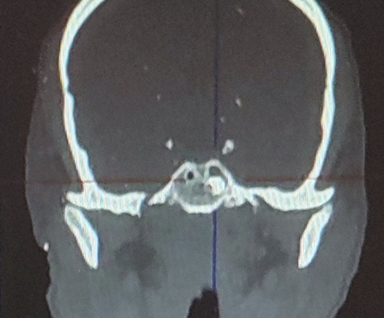

Клинический пример. Раненый П. с огнестрельным слепым ранением средней зоны лица и инородным телом клиновидной пазухи. По результатам КЛКТ головы выявлено инородное тело металлической плотности в левой половине клиновидной пазухи. Под общей анестезией эндоназальным доступом с помощью эндовидеоскопической техники через переднюю стенку выполнено удаление инородного тела. Операция прошла без осложнений.

Компьютерные томограммы раненого в трех проекциях с инородным телом клиновидной пазухи: